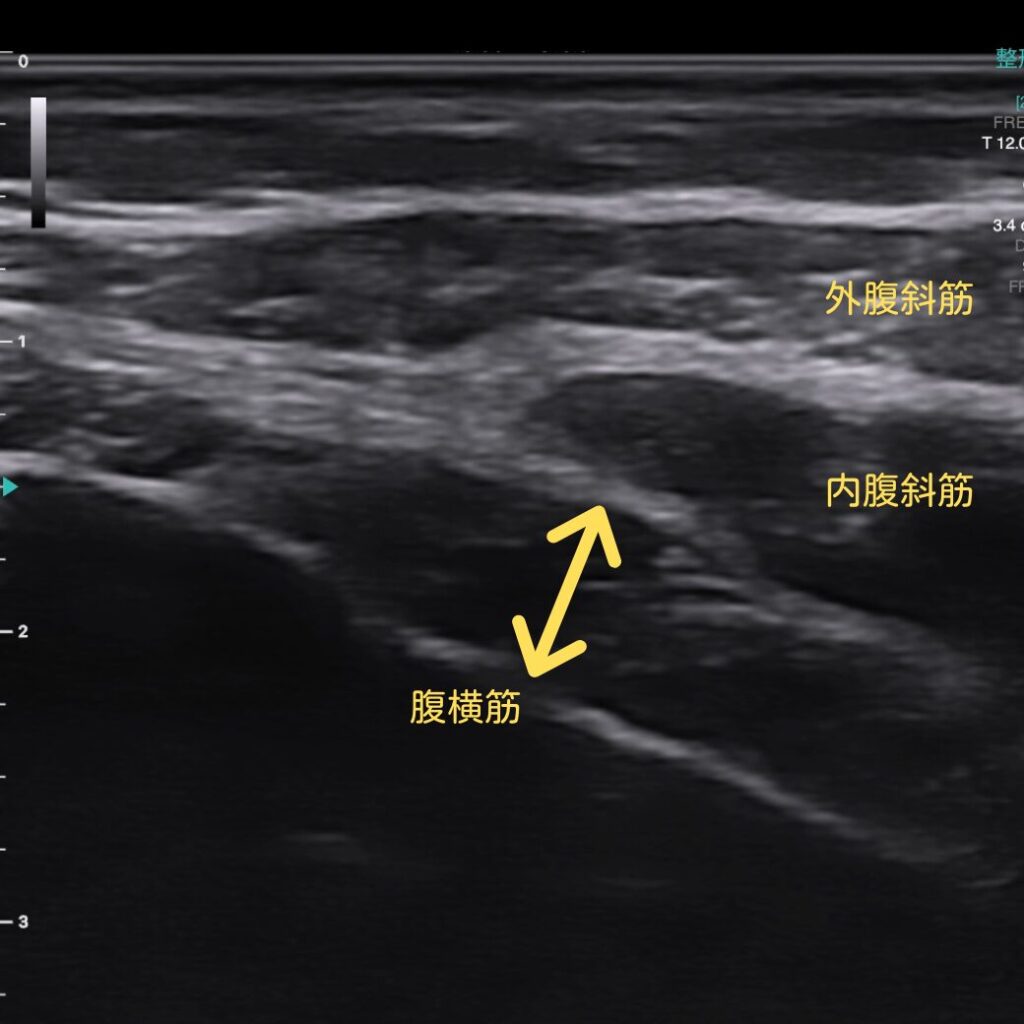

さらに、腹横筋(インナーマッスル)が実際に使えているか

超音波エコーでリアルタイムに“見える化”しながら確認できます。

「効いているつもり」を避け、確実に正しいトレーニング効果へつなげます。

エコーで確認すると、体幹が働いた瞬間がその場で見えます!